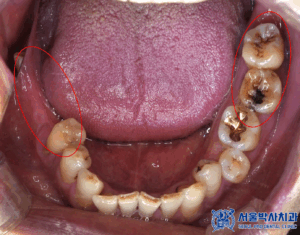

이번 환자분은

오른쪽 치아들이 많이 흔들려서

임플란트 상담을 받기위해

치과의사인 지인 소개로

산성역치과 서울박사에

내원해주셨습니다.

확인해보니,

치아가 상실된 부위도 많고

남아있는 치아들이

흔들리는 상황이였는데요.